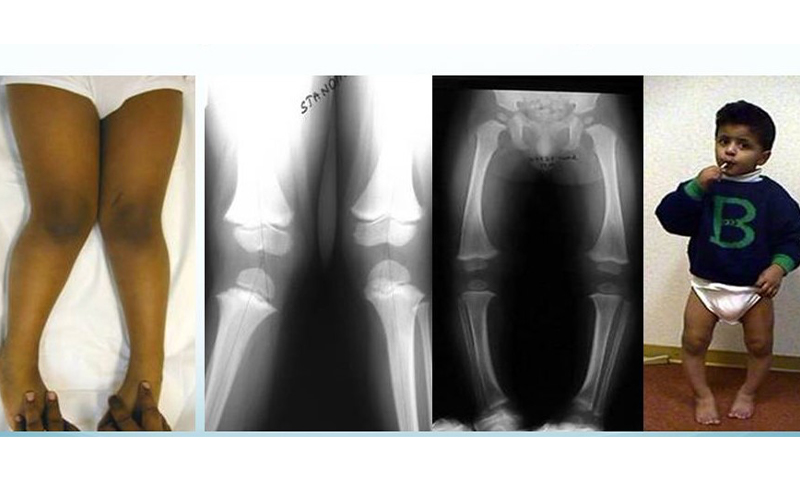

When it comes to bone and joint issues in children, seeking care from a specialist pediatric orthopedic surgeon is crucial for optimal treatment and long-term outcomes. Pediatric orthopedic surgeons have advanced training and expertise in addressing the unique needs of growing bones and joints. As children are still growing, their bodies response to injuries, infections, and deformities are different than a full grown person. In addition, the evaluation and treatment of a child is usually quite different than for an adult, even for the same problem.

• Has congenital orthopedic conditions like clubfoot or hip dysplasia.